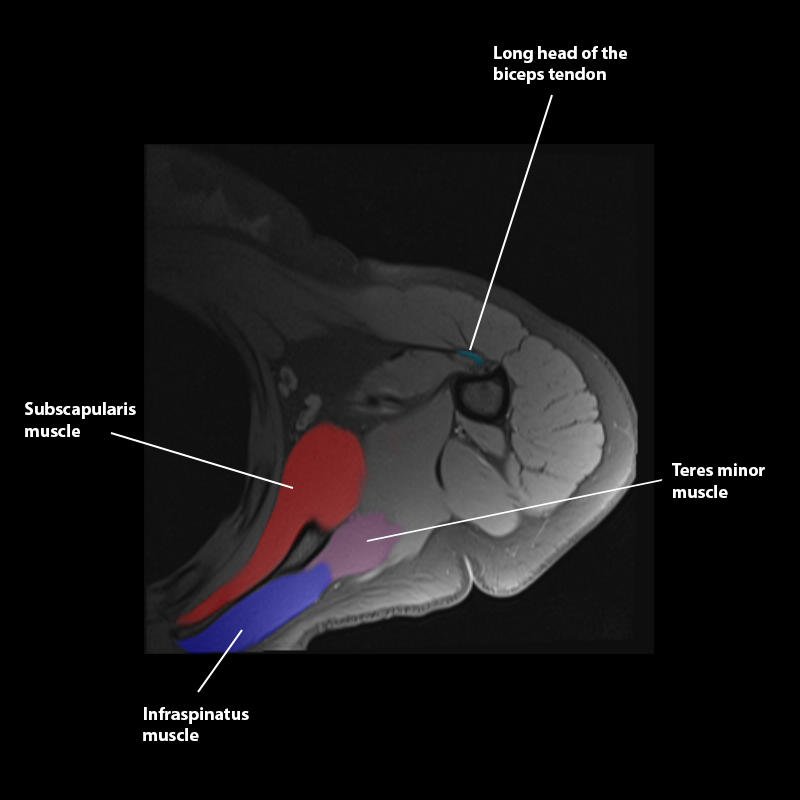

Shoulder MRI Anatomy